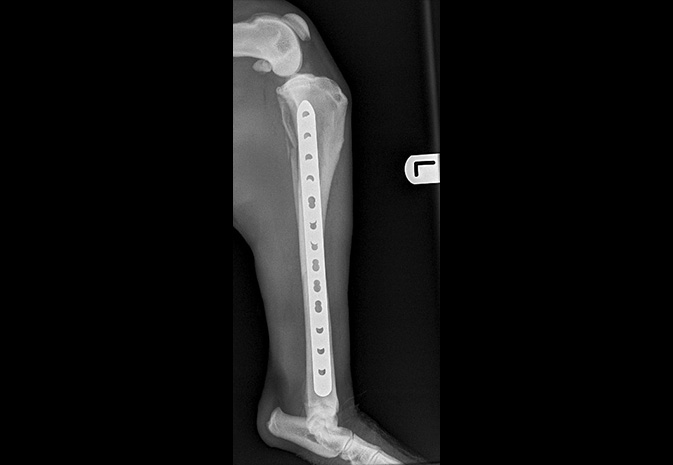

Fractures